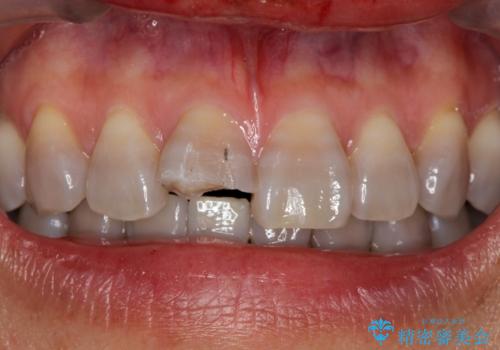

転んで前歯が折れた 色合いの難しい歯のセラミック修復

- 転倒し前歯を地面に強打して折れたとのことで来院。

幸い神経は生きており、セラミックでかぶせることになりました。

まず保険治療でコンポジットレジン修復を行い、神経の状態を確認した後、クラウンによる修復を行いました。